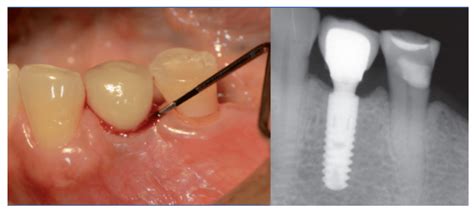

- Evaluación clínica de la encía: Primero, examinamos cuidadosamente la zona alrededor del implante. Observamos si hay enrojecimiento, inflamación o recesión de la encía, y si se produce sangrado al sondear. El sondeo periimplantario se hace con una sonda periodontal milimetrada, deslizando suavemente entre la encía y el implante para medir la profundidad de la bolsa. En un implante sano, la sonda penetra solo 2-3 mm y no hay sangrado. En la periimplantitis podemos encontrar bolsas profundas (por ejemplo >5 mm) y sangrado e incluso pus al sondear. La presencia de supuración (pus) al presionar la encía es prácticamente diagnóstico de infección activa.

- Medición de la profundidad del surco periimplantario: Como mencioné, usamos la sonda periodontal para medir la profundidad alrededor del implante en varios puntos. Un aumento de esa profundidad respecto a mediciones previas, o en comparación con parámetros normales, indica pérdida de inserción. Por ejemplo, profundidades mayores de ~5-6 mm con sangrado son indicativas de periimplantitis significativa.

Un aspecto del diagnóstico es determinar si el caso es solo mucositis (encía inflamada pero hueso intacto) o ya es periimplantitis (con pérdida ósea). Esto se clarifica combinando el sondeo y la radiografía. Si hay sangrado al sondeo pero la radiografía muestra el hueso intacto, hablaríamos de mucositis periimplantaria. En cambio, si la radiografía muestra periimplante con pérdida ósea (por ejemplo se ven expiras del implante descubiertas) junto con inflamación clínica, entonces es periimplantitis.